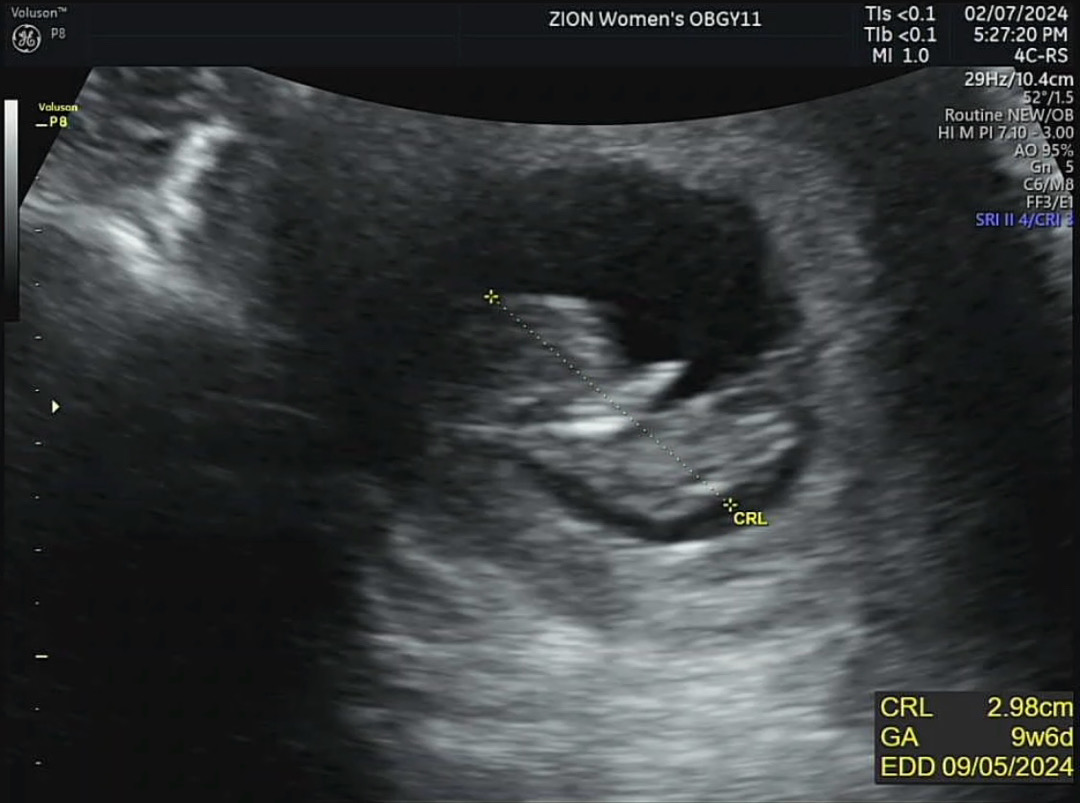

10주차 촘파 보고왔어요ㅎㅎ애기집이 작아서 애기가불편한건 아닌지 걱정되네여 10주차에 아기집크기가 이정도면 괜찮은걸까요?

저도 10주2일차 예요 ㅎㅎ 저도 어제 촘파보고왔는데 애 크기가 3.3cm...커서그런지...우디맘님 보다는 애기집이 좀더 크긴했어요 저크기에 저정도 애기집이면 괜찮은거같은데욥 ㅎㅎ병원에서 뭐라안하면 지켜봐도될꺼같아요^^ 전 애기집커지는거땨메 ㅜㅜ 생리통같은 통증이 있어서 엄청신경쓰여용...